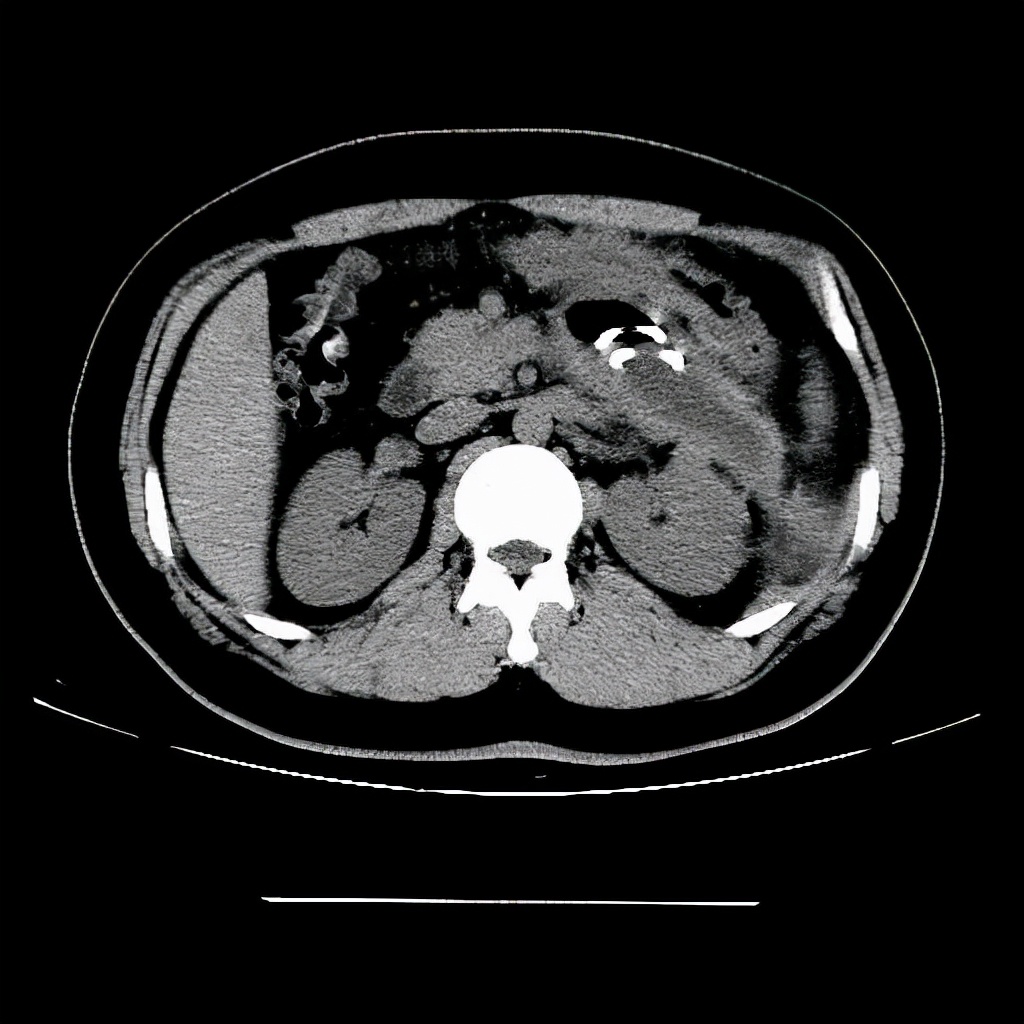

3、胰腺囊肿

胰腺囊肿和大多的良性囊肿是不同的,相对风险比较大。

如果是胰腺假性囊肿,可能是急性胰腺炎以及胰腺创伤导致的并发症,如果囊肿较小,在一两个月左右能够消失,也可以进行手术引流,因为囊肿破裂会出现感染。

需要提醒,如果存在通过鉴定是肿瘤性胰腺囊肿,会有癌变的可能,需要及时采取措施,毕竟胰腺癌被称之为"癌中之王"和胰腺相关病都不能忽略。